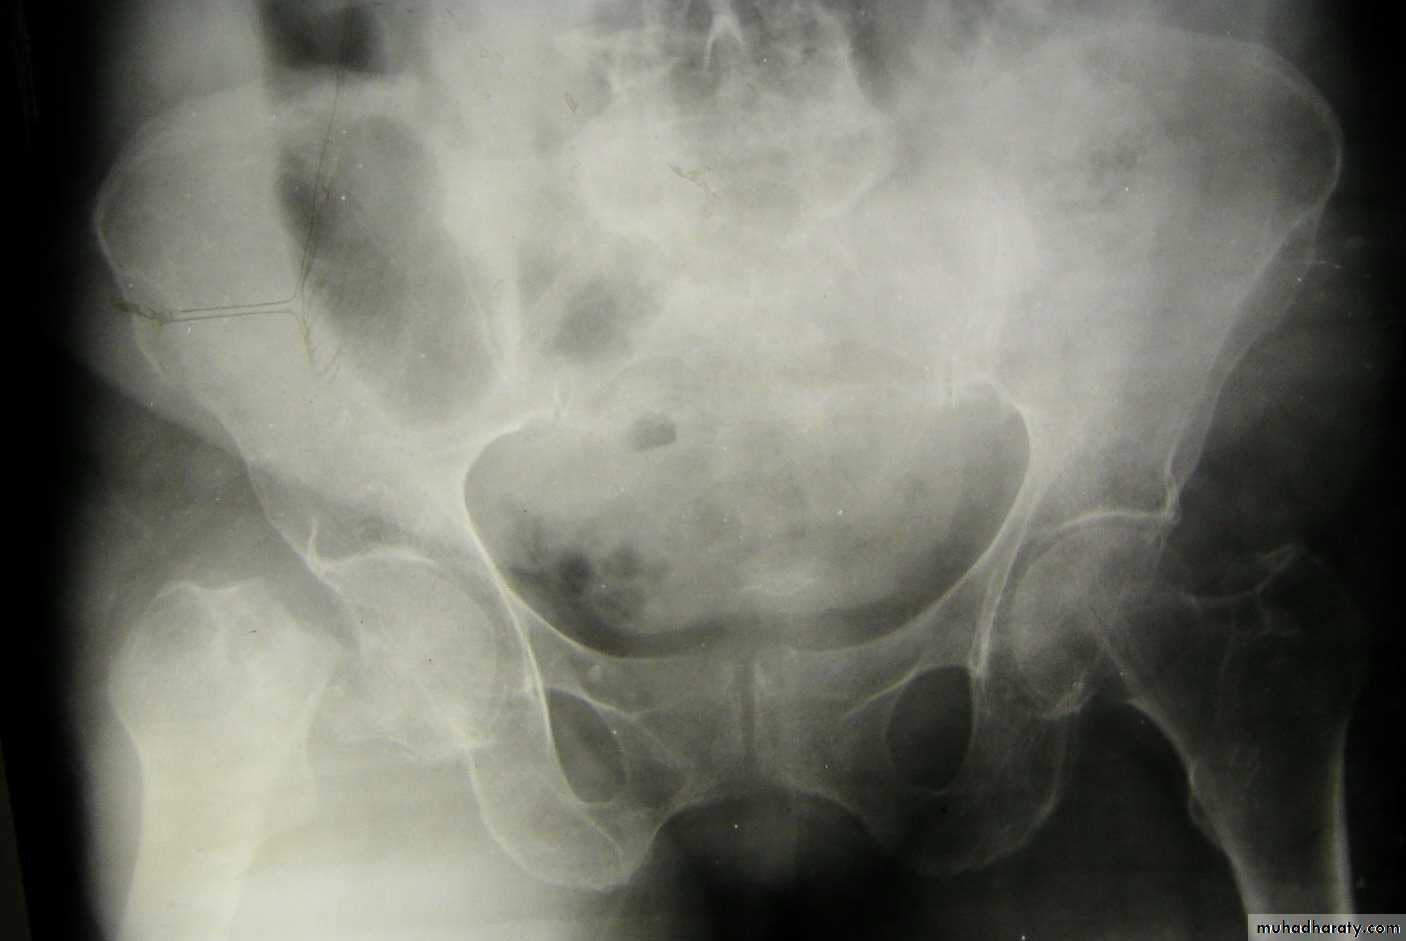

Traumatic anterior hip dislocation:Mechanism :

Road traffic accident ,miner, building laborer who is leg wide .

knees straight .

Back bent forward.

Clinically:

O\ELeg external rotation.

Abducted and slightly flexed.

Bulging head seen laterally and also feel.

Hip movement impossible.

Neurovascular examination necessary.

Radiological examination:

Hip dislocated either superior, inferior in relation to the acetabulum.Treatment: